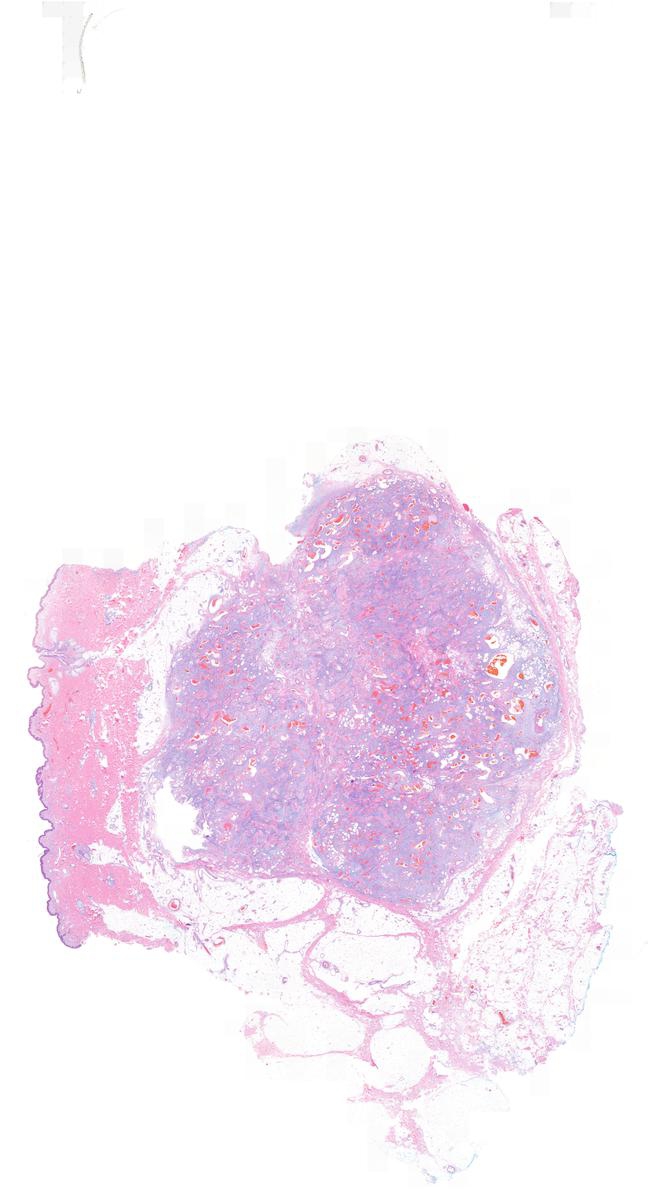

Myxoid spindle cell lipoma with desmin immunopositivity KiKo XP Spindle Cells Positive For Desmin Mpnsts are focally positive for s100 protein in <50% of cases and show loss of h3k27me3 expression. Immunostains lca, tdt, synaptophysin, myod1 and. If the cells in your sample produce desmin, your pathology report will describe the cells as positive or reactive. If they do not produce desmin, your. Spindle cells may be focally positive to epithelial markers such as. Spindle Cells Positive For Desmin.